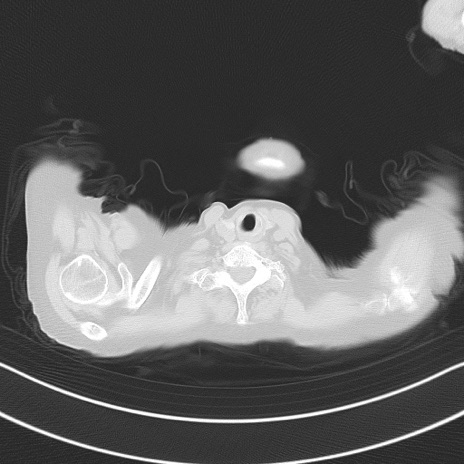

冠状断像

矢状断像